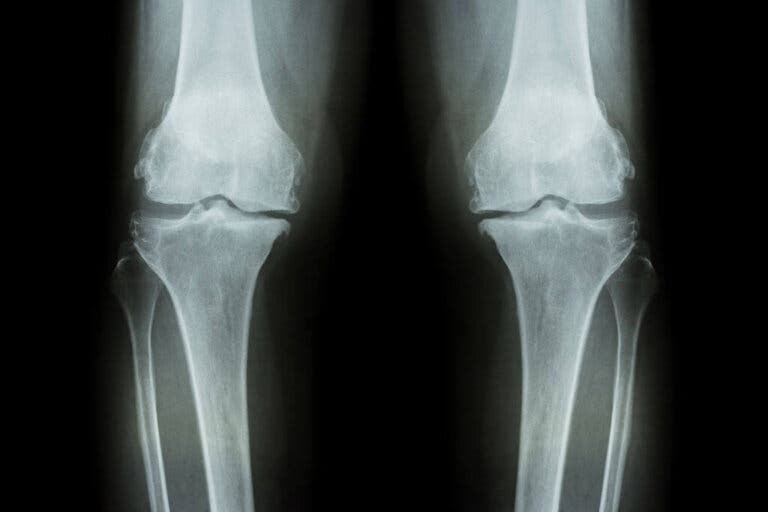

Sabemos que el desgaste de rodilla es una enfermedad crónica muy dolorosa e incapacitante, tanto que a largo plazo es posible sea necesaria una operación para recibir una prótesis de rodilla.

El desgaste de rodilla se debe a la artrosis. En muchas ocasiones factores genéticos y hereditarios juegan un papel muy importante, tal y como afirma este estudio de la Universidad de Santiago de Compostela; asimismo, factores como la obesidad donde las rodillas soportan un peso muy elevado. Pero dentro de la enfermedad articular hay ocasiones donde se desconoce su origen.

Pueden existir alteraciones dentro de las células del cartílago articular, una alteración de los llamados condrocitos y del hueso subcondral, que deriva en una temida falta de resistencia a la presión y la falta también de la elasticidad del cartílago, que se va deteriorando y adelgazando.

Tampoco podemos pasar por alto la artrosis relacionada con el envejecimiento, donde la salud del cartílago va sufriendo cambios degenerativos.

Otra de las causas puede ser una lesión e incluso una anomalía previa de la propia articulación. Es lo que se conoce como artrosis de rodilla secundaria y se sucede básicamente por lesiones en el menisco, fracturas, problemas en las articulaciones a raíz de sobre esfuerzos, como es el caso de los deportistas o personas obesas.